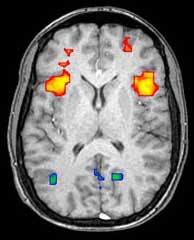

Functional magnetic resonance imaging

Functional magnetic resonance imaging (fMRI) and arterial spin labeling (ASL) relies on the paramagnetic properties of oxygenated and deoxygenated hemoglobin to see images of changing blood flow in the brain associated with neural activity. This allows images to be generated that reflect which brain structures are activated (and how) during performance of different tasks or at resting state. According to the oxygenation hypothesis, changes in oxygen usage in regional cerebral blood flow during cognitive or behavioral activity can be associated with the regional neurons as being directly related to the cognitive or behavioral tasks being attended.

Most fMRI scanners allow subjects to be presented with different visual images, sounds and touch stimuli, and to make different actions such as pressing a button or moving a joystick. Consequently, fMRI can be used to reveal brain structures and processes associated with perception, thought and action. The resolution of fMRI is about 2-3 millimeters at present, limited by the spatial spread of the hemodynamic response to neural activity. It has largely superseded PET for the study of brain activation patterns. PET, however, retains the significant advantage of being able to identify specific brain receptors (or transporters) associated with particular neurotransmitters through its ability to image radiolabelled receptor "ligands" (receptor ligands are any chemicals that stick to receptors).

As well as research on healthy subjects, fMRI is increasingly used for the medical diagnosis of disease. Because fMRI is exquisitely sensitive to oxygen usage in blood flow, it is extremely sensitive to early changes in the brain resulting from ischemia (abnormally low blood flow), such as the changes which follow stroke. Early diagnosis of certain types of stroke is increasingly important in neurology, since substances which dissolve blood clots may be used in the first few hours after certain types of stroke occur, but are dangerous to use afterwards. Brain changes seen on fMRI may help to make the decision to treat with these agents. With between 72% and 90% accuracy where chance would achieve 0.8%,[13] fMRI techniques can decide which of a set of known images the subject is viewing.[14]